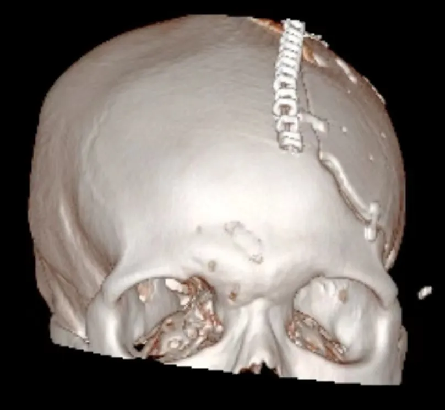

患者术后满三个月再次返院进行颅骨缺损修补术,经过完善术前检查、全科讨论、做好充分手术准备后,武宁县总医院人民医院院区神经外科团队成功为患者完成自体颅骨修补术。

术后: